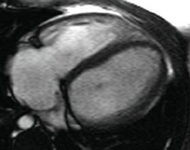

Ressonância nuclear magnética (RNM) em um paciente com regurgitação pulmonar após reparo de tetralogia de Fallot. O paciente tem ventrículo direito não restritivo e a RNM mostra ventrículo direito dilatado

De: Chaturvedi RR, Redington AN. Heart. 2007 Jul;93(7):880-9; usado com permissão